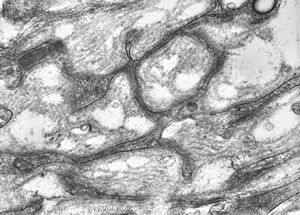

M,26y. | a periphery of a glial scar

M,26y. | a periphery of a glial scar

M,26y. | periphery of a glial scar